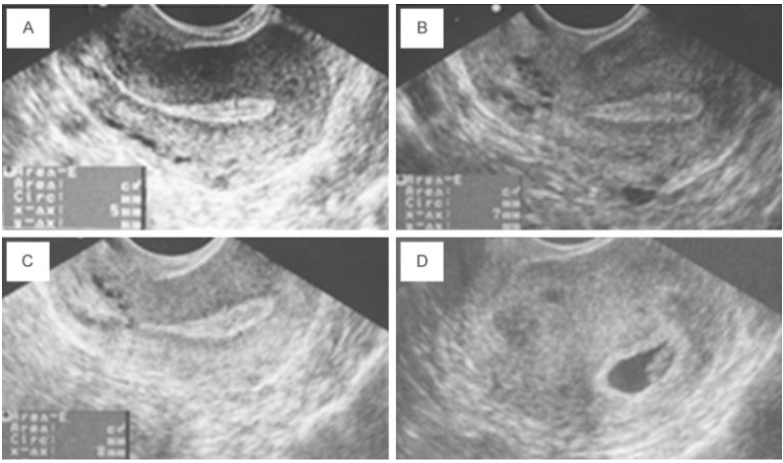

Endometrial lining is a key factor in pregnancy and lives birth outcome. A study conducted in 2015 showed that women treated with PRP, who had previously failed endometrial lining growth after conventional estrogen therapy treatments, had great success with PRP therapy. Out of five patients that had exceptionally poor lining growth, four of them continued to have a successful pregnancy. You can see the increased lining of the endometrium in the pic below.

(A) Lining prior to treatment. (B) Lining after round 1 of PRP (C) Lining after round 2 of PRP (D) Intrauterine sac at 6 weeks pregnancy Chang Y, Li J, Chen Y, et al. Autologous platelet-rich plasma promotes endometrial growth and improves pregnancy outcome during in vitro fertilization. International Journal of Clinical and Experimental Medicine. 2015;8(1):1286-1290.